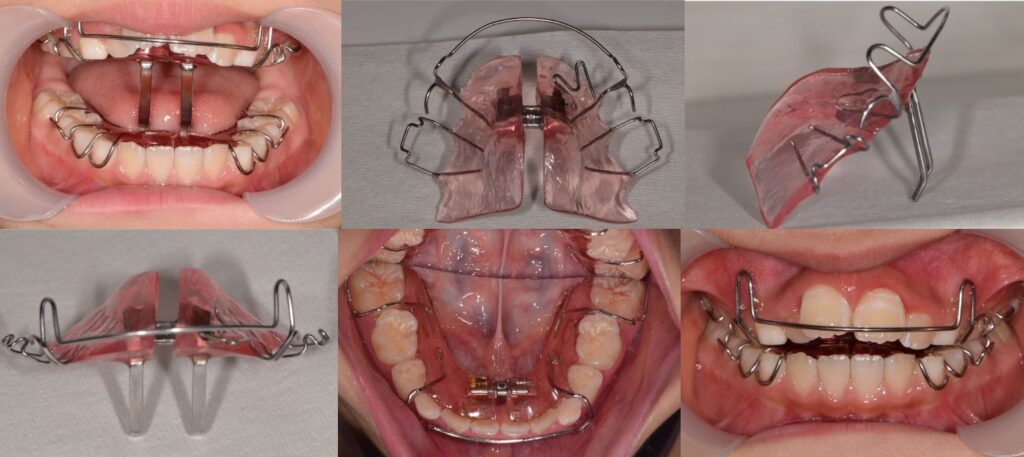

小児矯正

| 診断 | 下顎劣成長による口呼吸 上顎歯列叢生 |

| 処置内容 (または主訴) | 下顎の前方成長を促す床矯正(BJA) 上顎歯列の拡大を行い鼻腔解放 MFTを行い鼻呼吸を促す 舌の機能訓練を行い弄舌癖の是正 |